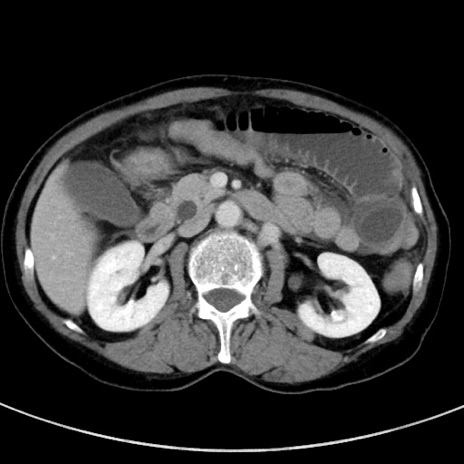

冠状断像

【症例】70歳代女性

【主訴】下腹部痛・嘔吐

【現病歴】2日前より腹痛あり。昨日嘔吐あり。症状改善しないため来院。

【既往歴】胃GISTに対して胃部分切除後。

【身体所見】BT 37.1℃、BP 128/77mmHg、腹部:平坦・軟、下腹部に圧痛あり。

【データ】WBC 10200、CRP 0.31